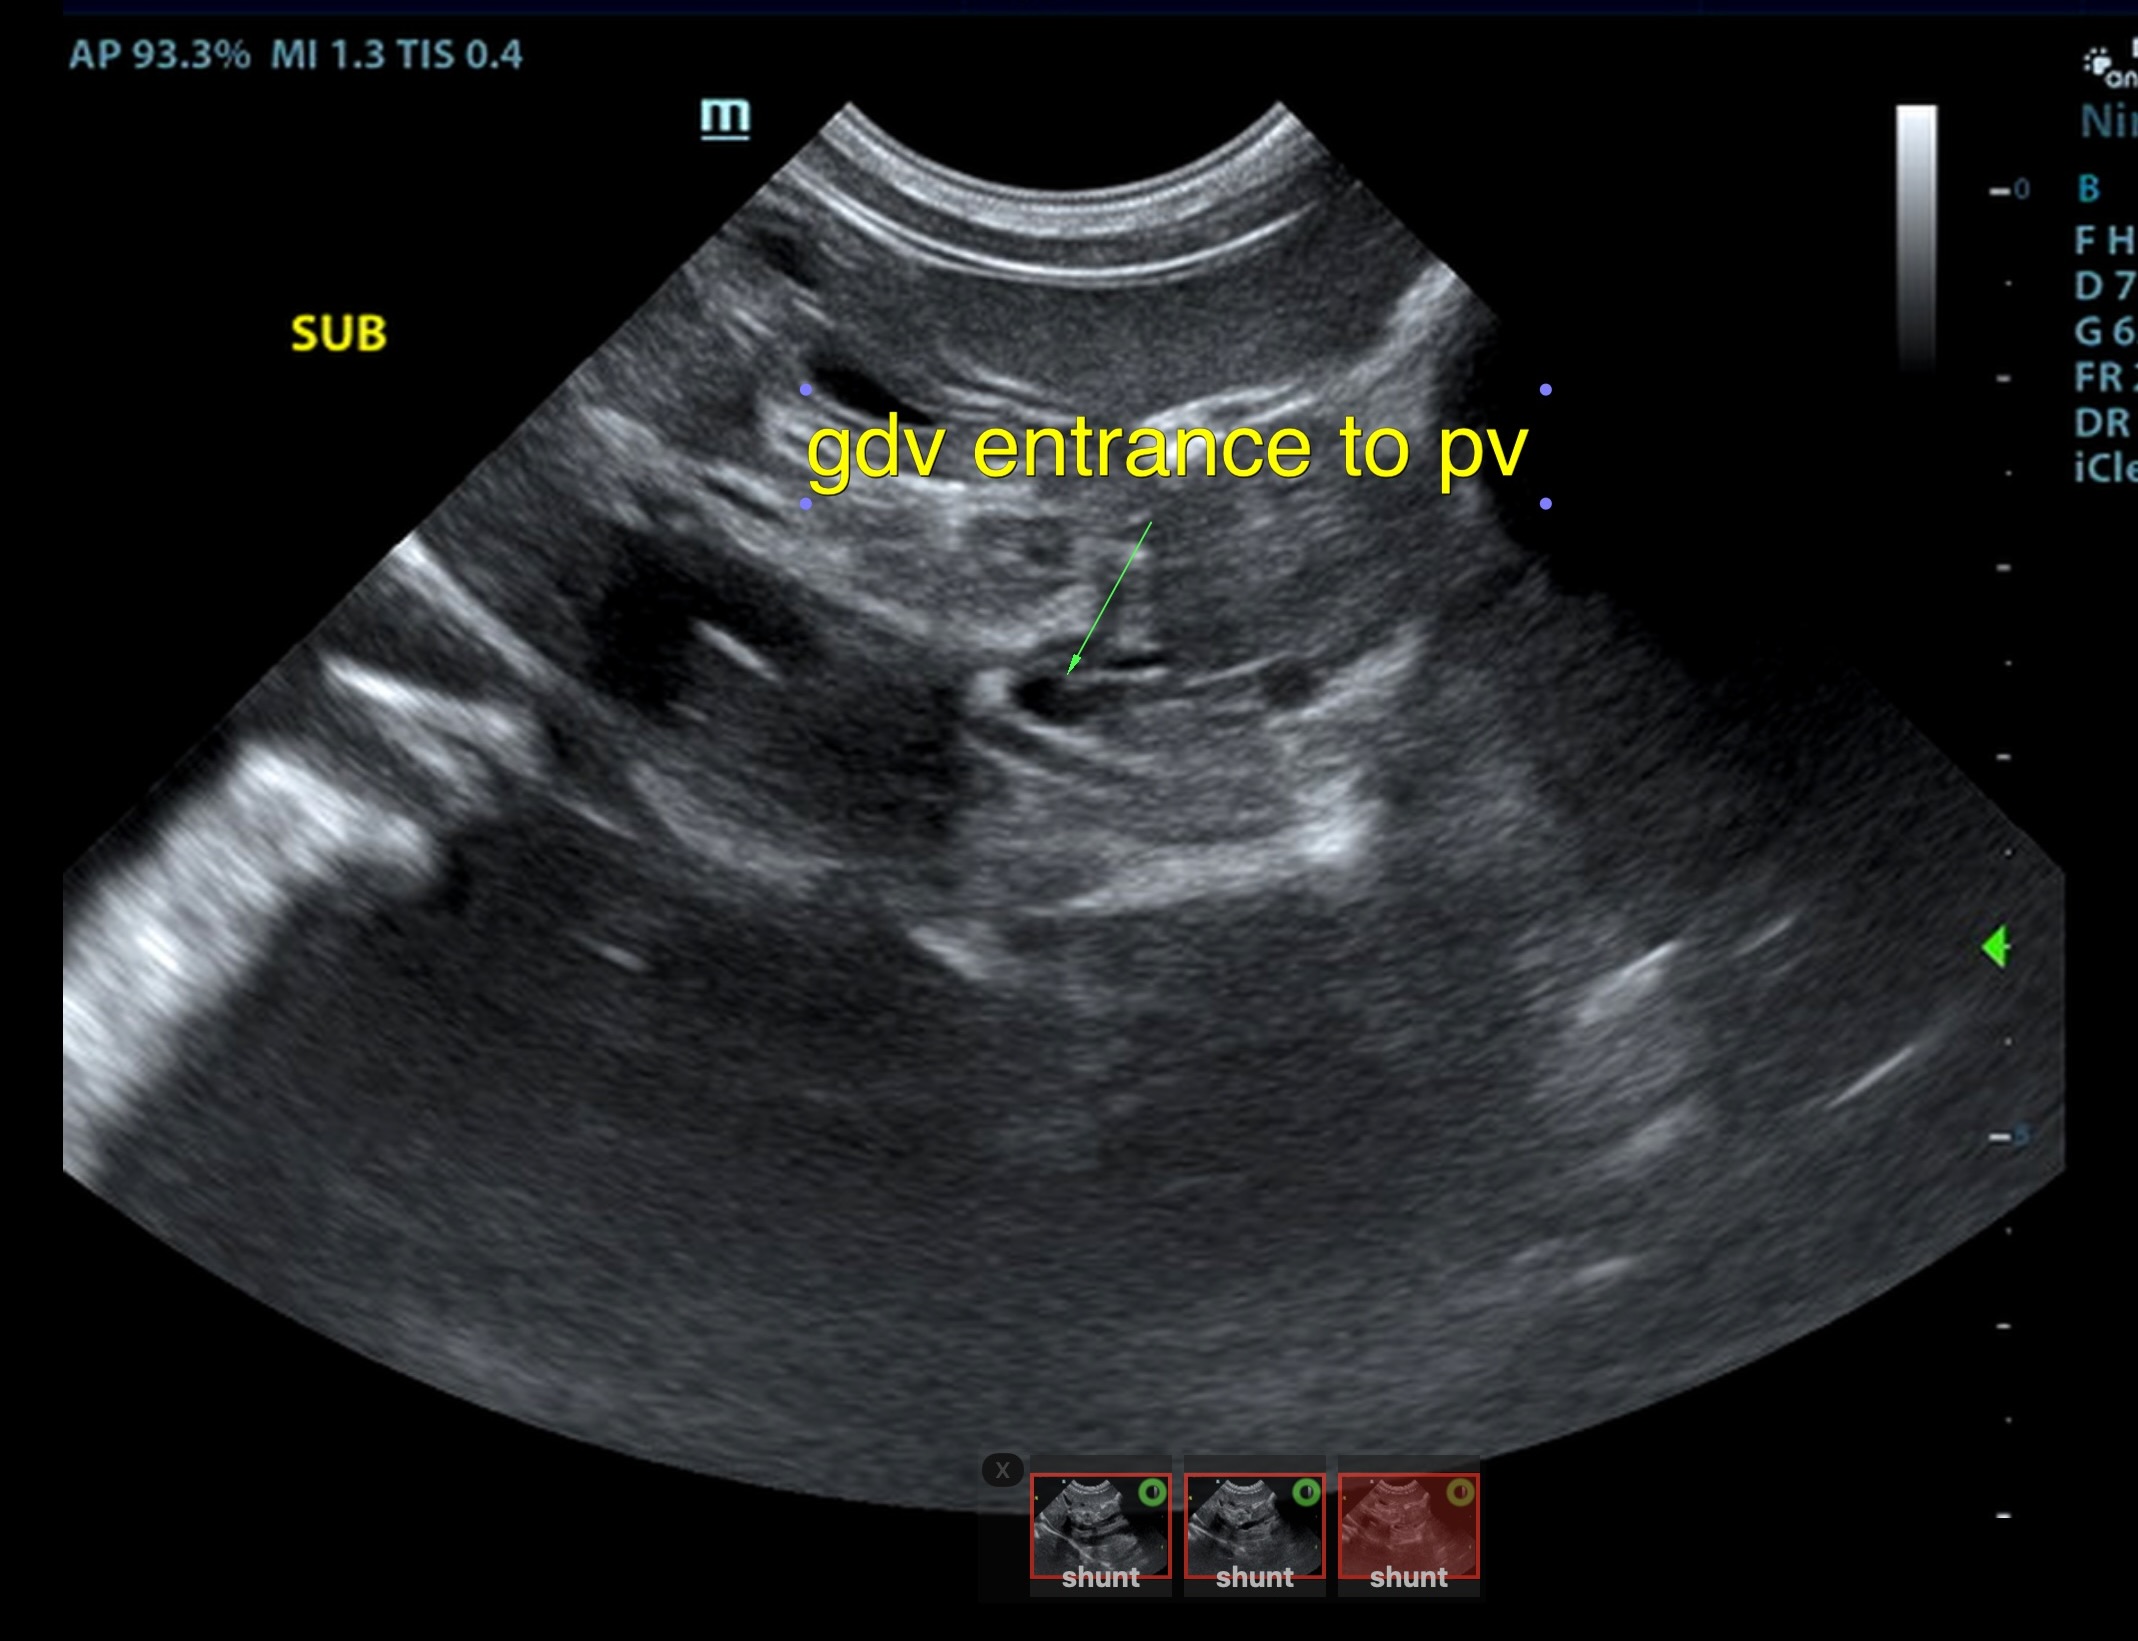

The liver was subnormal in size, yet the portal vein and vena cava ratio was 1:1. The portal veins were subnormal in size and measured 0.34 cm. The vena cava was enlarged and measured 0.34 cm. The vena cava was enlarged and measured 0.72 cm, aorta measured 0.4 cm. The branching of the portal vein appeared to be normal and of adequate volume. The portal vein and vena cava measured 0.5 cm each in the extrahepatic space. The splenic vein entry into the portal vein and gastroduodenal vein entry into the portal vein appear to be normal. There was one turbulent vessel in the region of the central branch of the portal vein, which may represent an intrahepatic shunt, but this could not be confirmed. The width of the shunt is approximately 0.76 cm. This is in position of central divisional shunt; however, right divisional origin cannot be completely ruled out. The gallbladder presented acceptably thin walls with primarily anechoic content. The cystic and common bile ducts were normal.